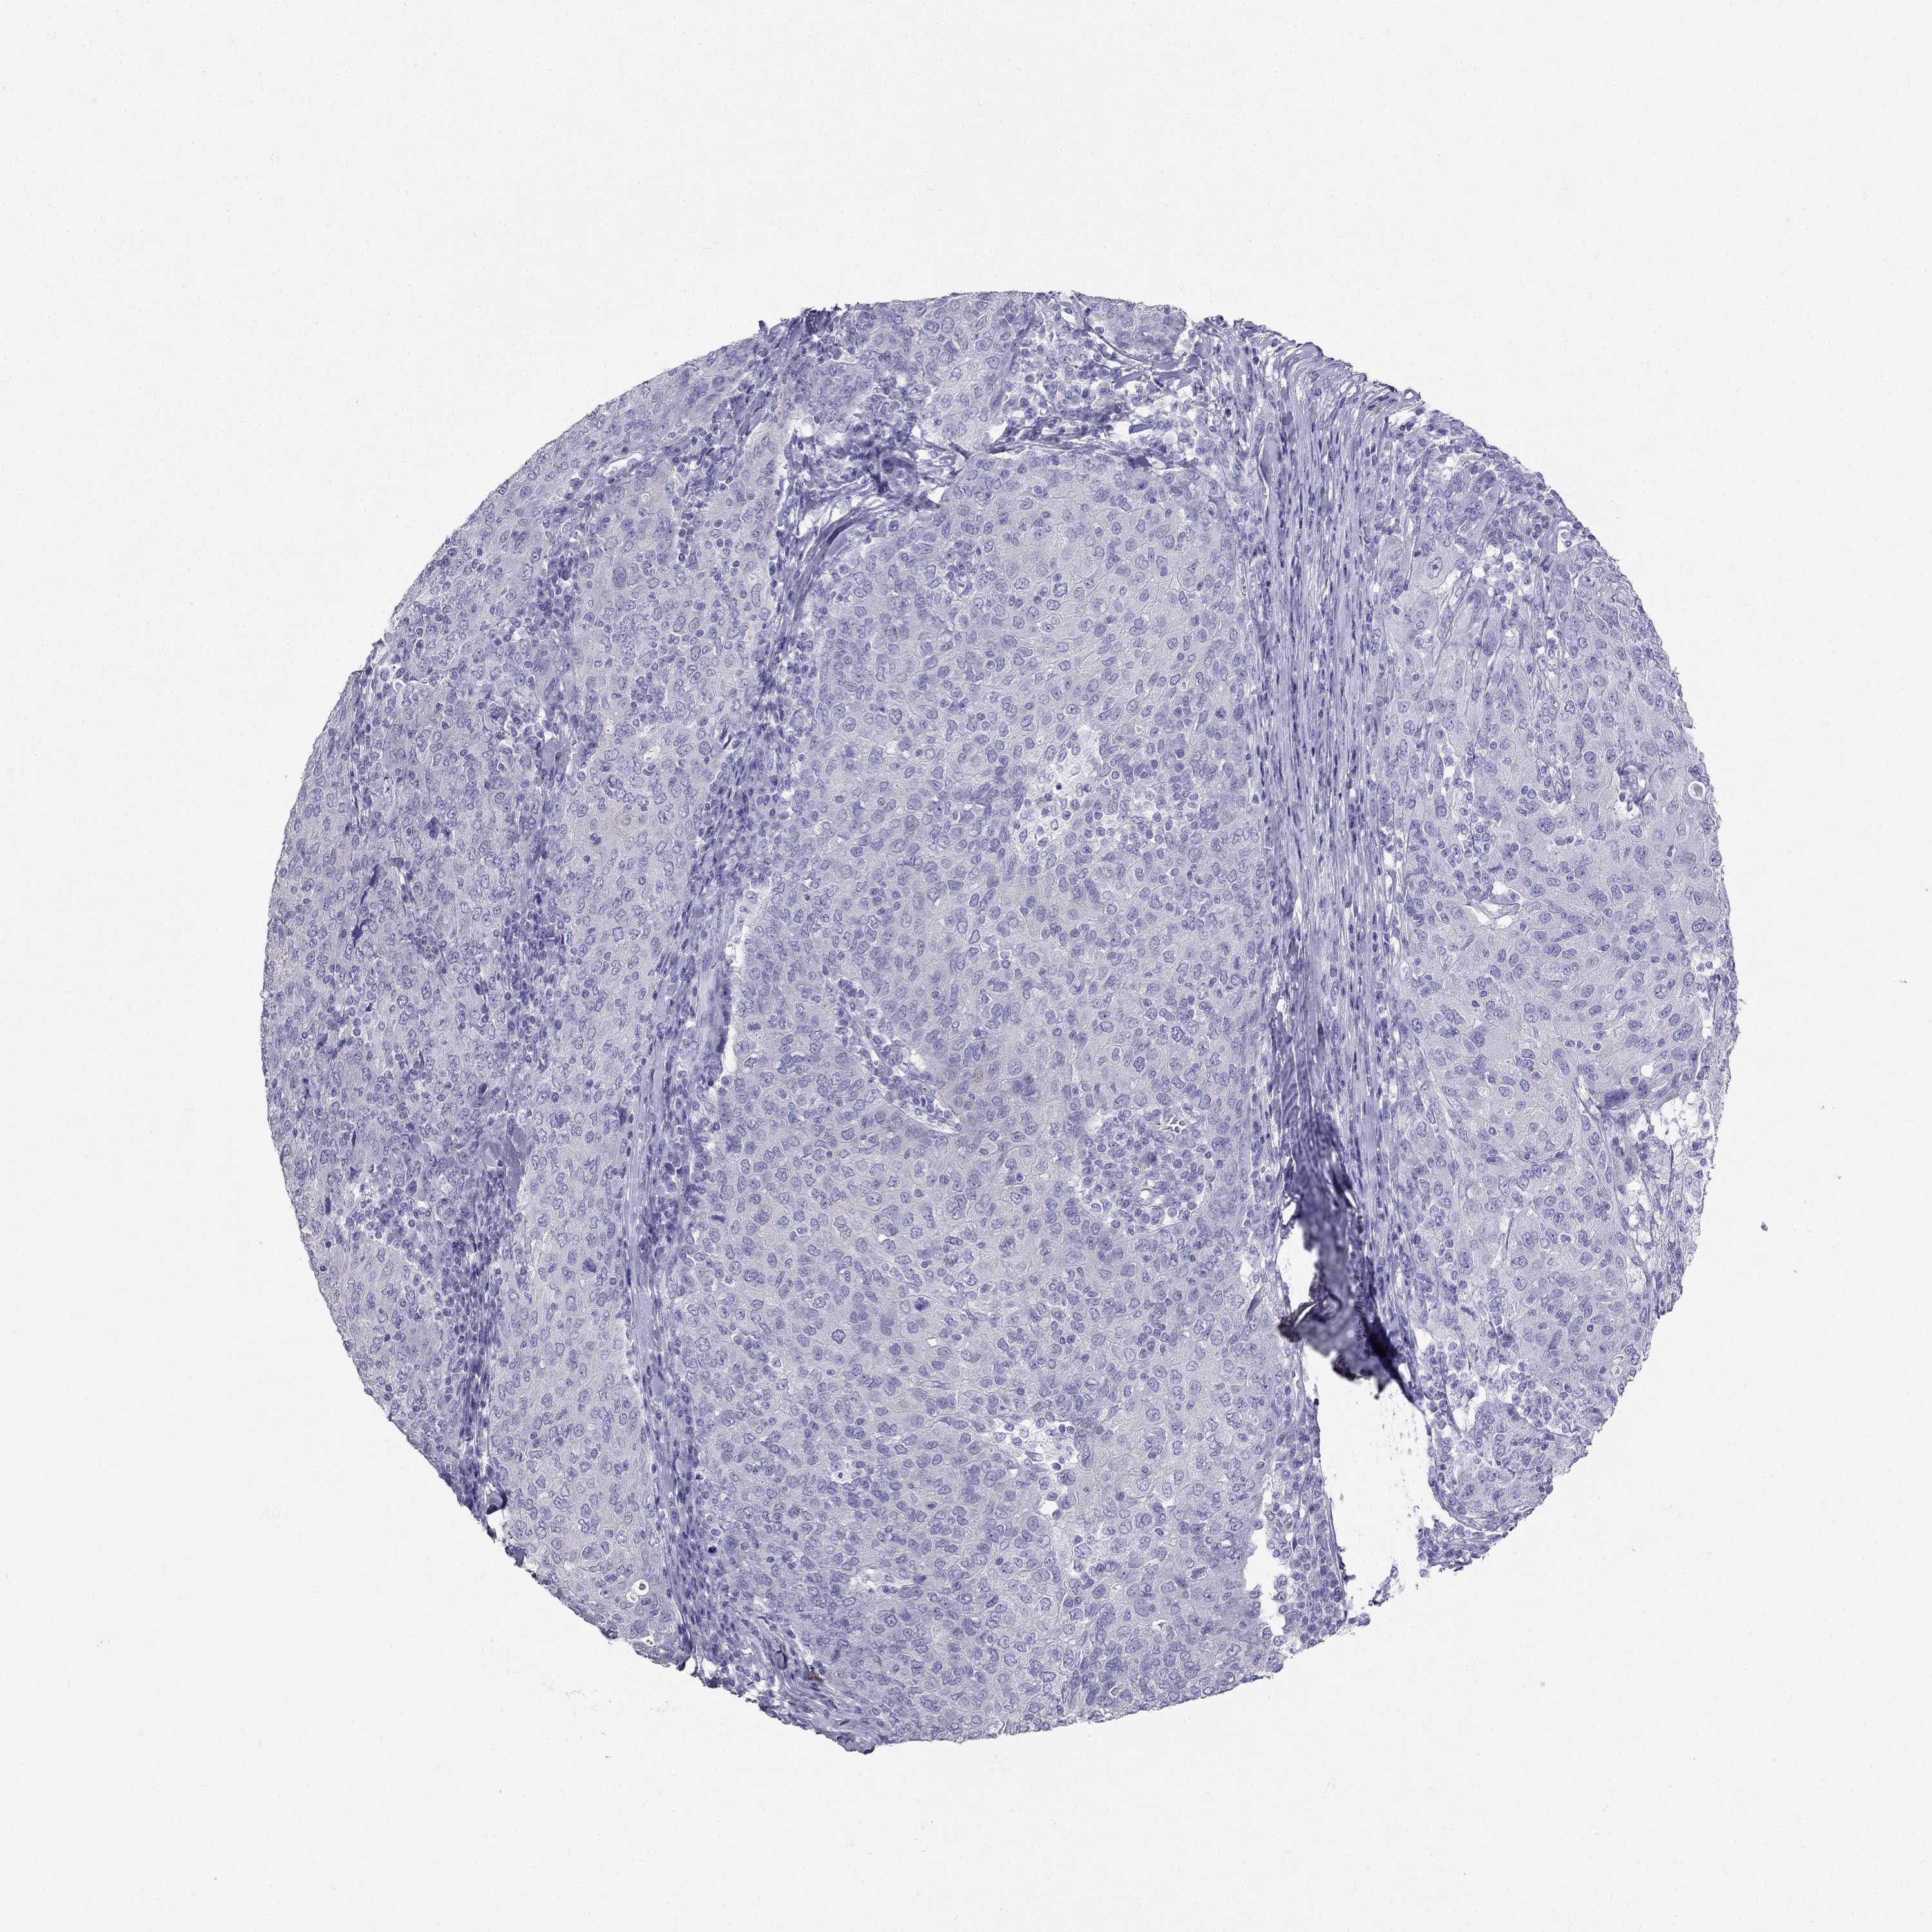

RFLNA